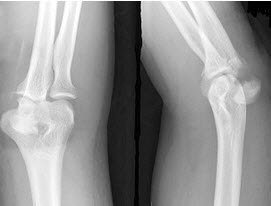

15、单项选择题

男,38岁,右肘关节外伤,结合图像,最可能诊断是()

A.肱骨外侧髁骨折

B.尺骨鹰嘴骨折

C.肱骨内侧髁骨折

D.肘关节脱位

E.未见异常